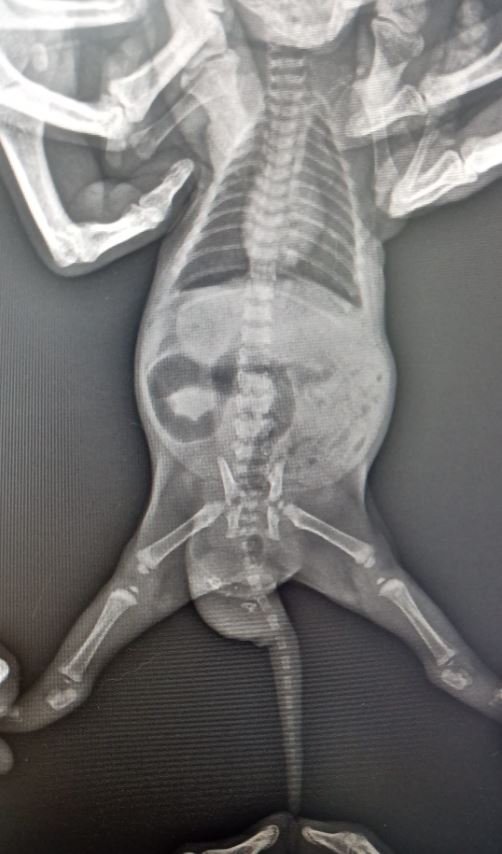

Büşra Nur Yıldız'ın siyam cinsi kedisi, yaklaşık 4 ay önce doğum yaptı. Doğan 2 yavru kediden birinin kuyruğunda şişlik olduğunu fark eden Yıldız, veterinere başvurdu. Veterinerde yapılan kontrolde kedinin kuyruğunda; dişleri, tüyleri, iskelet sistemi, kanal hücreleri oluşan yavru taşıdığı ortaya çıktı. Yavru kediye "teratom" (canavar tümör) tanısı konuldu. Kedi cerrahi operasyona alınarak, tümör temizlendi. Şu an 4 aylık olan kedi, sağlığına kavuştu.

Ameliyatı gerçekleştiren veteriner hekimlerden Emir Düzgören, kedi ile ilgili vaka bildirim raporu hazırlayacaklarını belirterek, "Yavruyu anesteziye uygun hale geldiğinde röntgene aldık ve içeride kemik benzeri dokular olduğu tespit edildi. Ardından çocuğun kuyruğunun alt bölümüne teratom tanısı konuldu. Çoğalan hücrelerden birinin bir tümör hücresine dönüşmesi sonucu oluşmuş. Bu çocukta hem deri, kıl, kemik, kanal hücrelerinin tamamı gelişen canavar tümör oluşmuş. Kardeşi gibi düşünebiliriz; ama tıbbi olarak aslında bir tümör. Bilinen tek vaka bildirimi bizim dışımızda yurt dışında var. Vaka bildirim raporu hazırlayacağız, bunu bilimsel dergilere göndereceğiz. İkinci vakanın da gerçekleştiğini dünyadaki tüm veteriner camiası bilecek. Operasyon çok başarılı geçti. Diğer kardeşi ile aynı, operasyon izi dahi kalmadı. Çok heyecanlandık. Muhtemelen meslek hayatımızda bir daha böyle bir vakaya denk gelmeyeceğiz. Belki Türkiye'de bile bir daha böyle bir vaka olmayacak. Bize denk geldi" dedi.